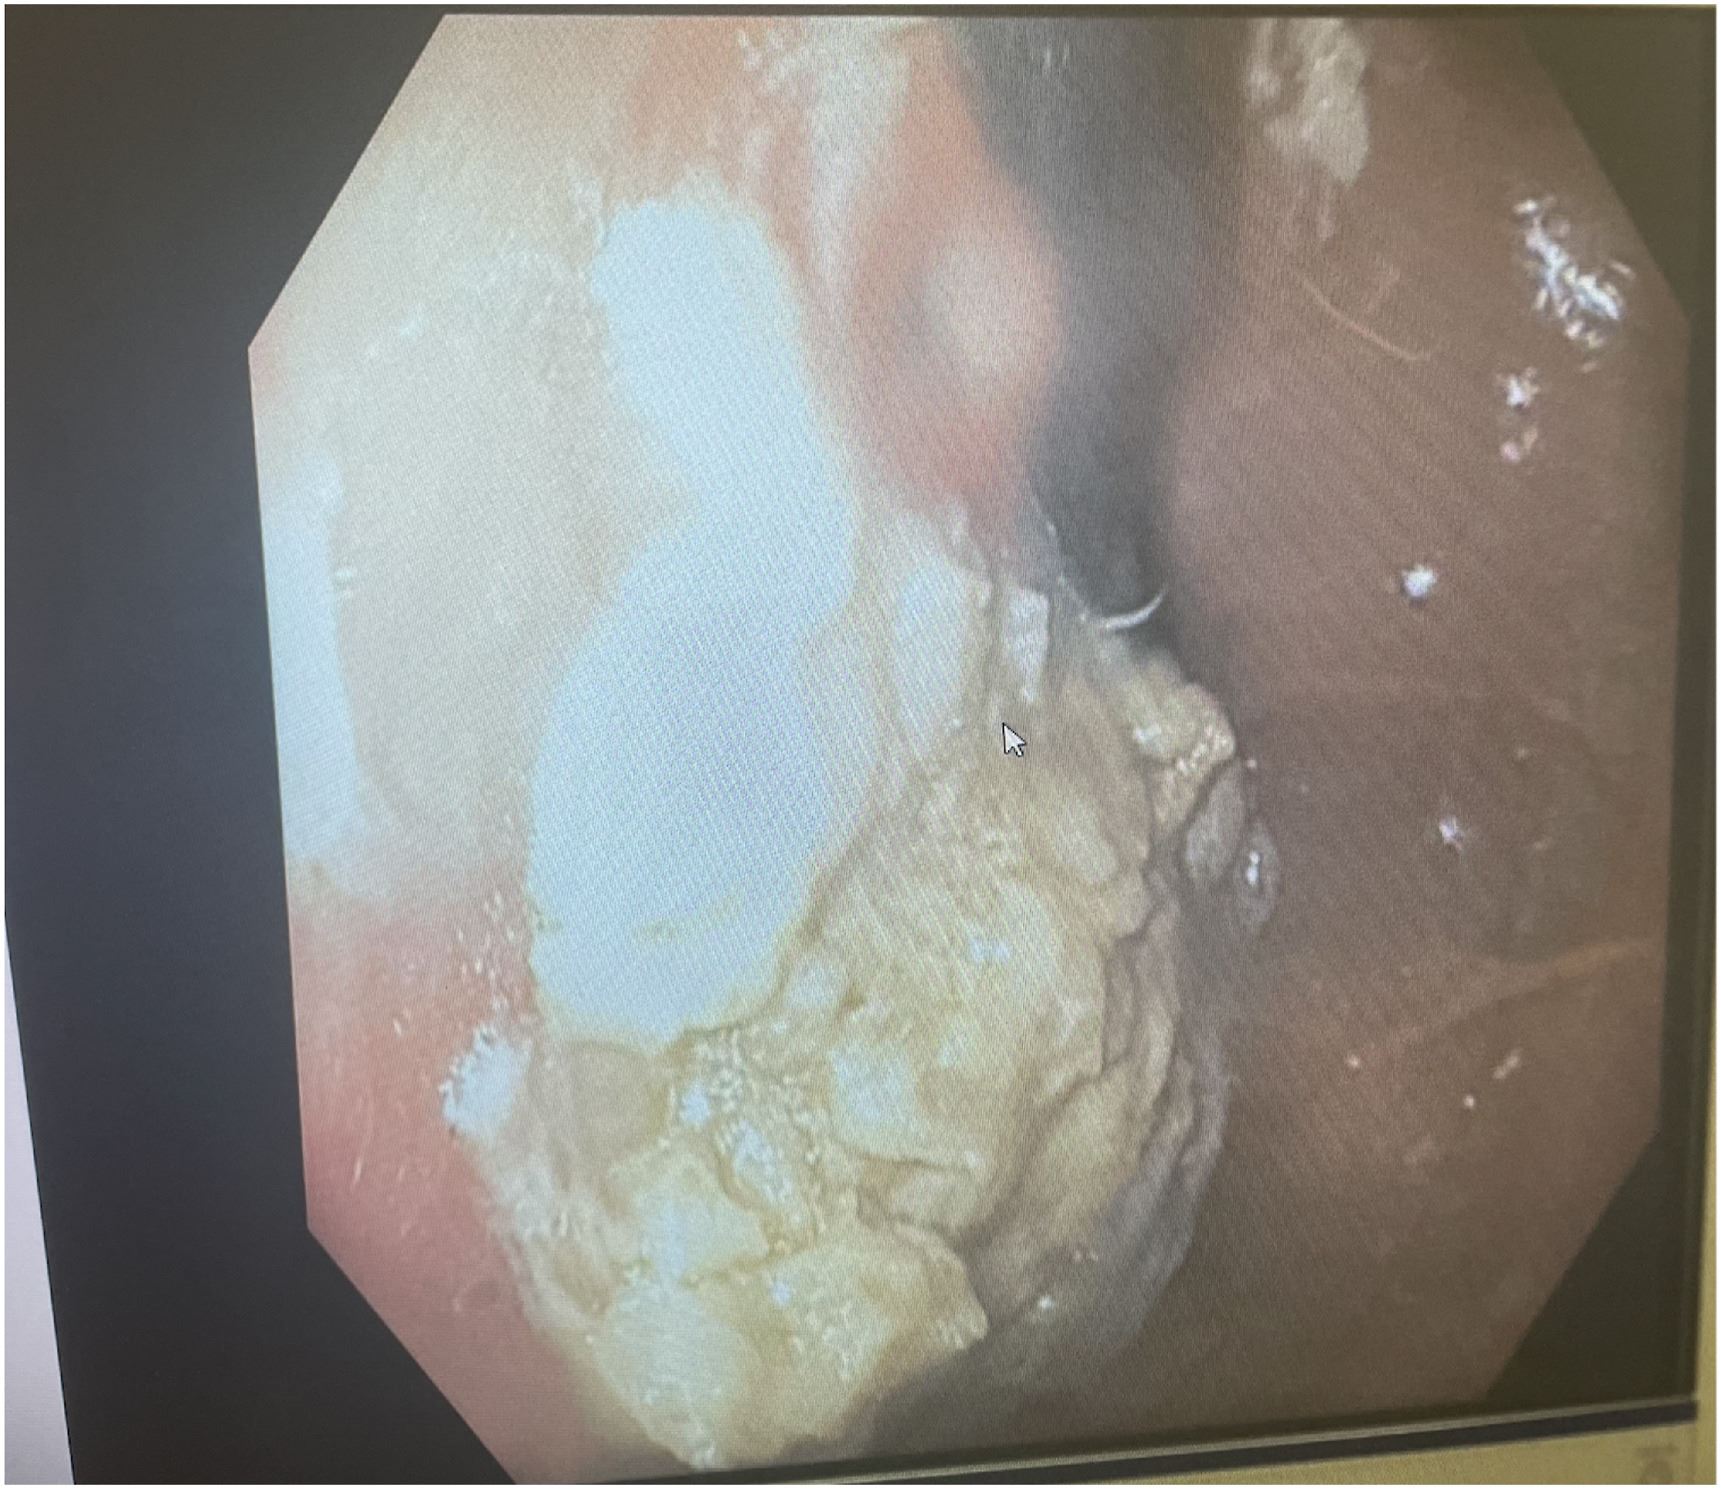

Ekoran itu, pasukan doktor yang diketuai oleh Dr. Chizite Iheonunekwu di Klinik Cleveland mula melakukan prosedur pembedahan dan menarik keluar gumpalan gula-gula menerusi kerongkong beliau.

Jelas doktor, gumpalan gula-gula yang disebut sebagai bezoar tersekat pada perut kanak-akanak ini hingga mengambil kira-kira 25 peratus ruang.

Dengan menggunakan skop khas, doktor kemudian mengeluarkan gumpalan berkenaan melalui esofagus atau kerongkong. Prosedur itu terpaksa dilakukan berulang kali bagi mengeluarkan kesemua gula-gula getah yang tersumbat.